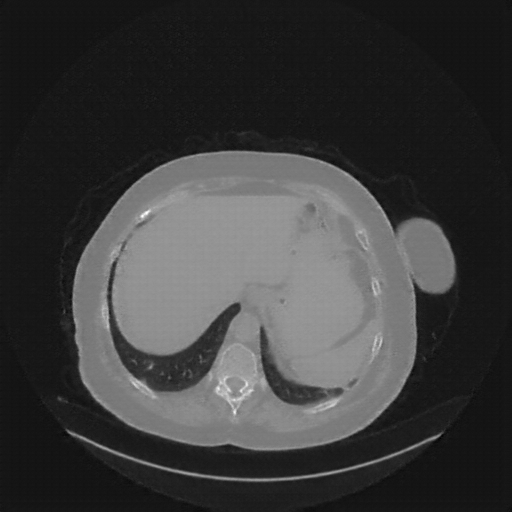

Original NATIVE CT scan (input)

No window - Raw intensity values

Lung window (WL -600, WW 1500 β†’ Low βˆ’1350, High +150)

Mediastinum window (WL 40, WW 400 β†’ Low βˆ’160, High +240)